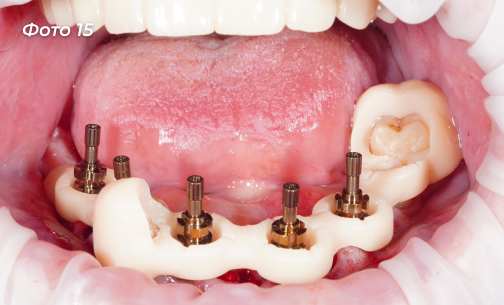

Изготовлена и установлена временная конструкция на нижнюю челюсть (Фото 14, 15).